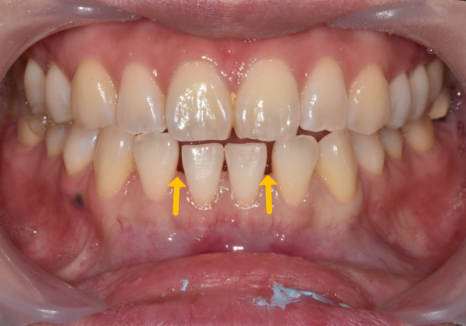

231017(전) 231116 (후)

다만, 어디까지 무삭제 또는 최소 삭제가 가능한지는

전체적인 교합 상태나,

치아가 얼마나 삐뚤어져 있는지까지

함께 보고 판단하는 것이 안전합니다.